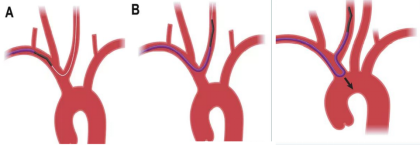

1、全麻下桡动脉入路:利用超滑导丝交换技术直接送入5F中间导管(下图1)。

2、中间导管到位造影基底动脉闭塞,向左侧椎动脉返流(下图3)。

3、微导管造影:微导管位于真腔,右侧大脑后动脉P3段(箭头所指)闭塞(下图2、4)。

4、支架释放:4*20取栓支架送入后可见血流通畅,左侧大脑后动脉仍闭塞。取栓后基底动脉通畅大脑后动脉P3段闭塞(下图5)。

决定取栓,微导丝通过,少量血流通过,血栓(箭头所指)更加明显了,回撤支架后造影:血流通畅,血管痉挛解除。

对于本次病例直接中间导管建立通路,中间导管到位造影基底动脉闭塞,4*20mm支架基底动脉取栓,小支架3*15mm大脑后动脉钳夹取栓。3*15mm小支架对血管刺激性更小,取栓术后血流通畅,未出现与支架相关并发症,且一把拉通,是远端血管取栓的一个选择。